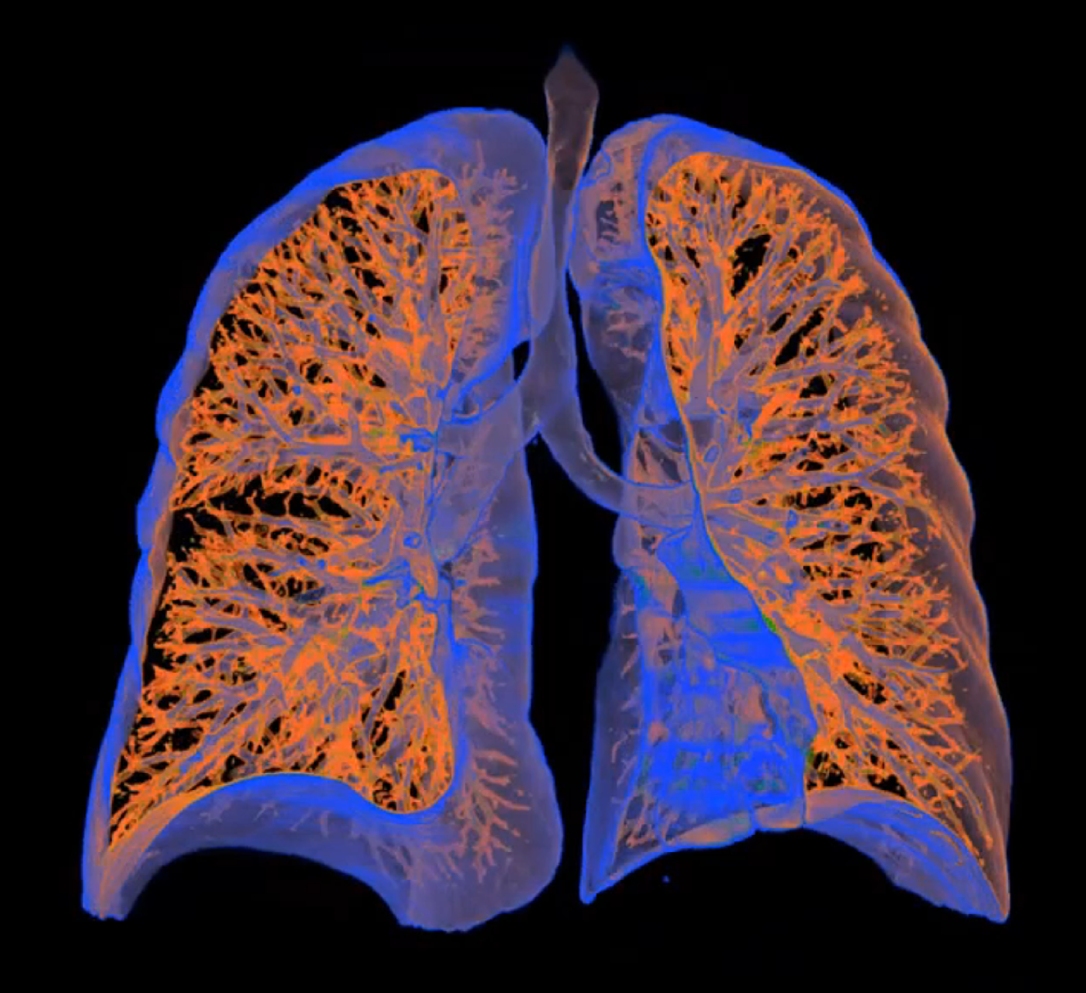

Μία προληπτική αξονική τομογραφία τον χρόνο μπορεί να ανιχνεύσει τον καρκίνο του πνεύμονα σε τόσο πρώιμο στάδιο, ώστε οι οκτώ στους δέκα ασθενείς βρίσκονται ακόμα εν ζωή 20 χρόνια αργότερα!

Σε πολλές περιπτώσεις δε, τον εντοπίζει πριν καλά-καλά γίνει συμπαγής όγκος, με αποτέλεσμα να εκμηδενίζει τον κίνδυνο θανάτου στην 20ετία.

Η εξέταση αυτή έχει καθιερωθεί εδώ και αρκετά χρόνια στις ΗΠΑ και σε άλλες χώρες ως προσυμπτωματικός – προληπτικός έλεγχος για τον καρκίνο του πνεύμονα. Και αυτό, διότι ο καρκίνος του πνεύμονα δεν προκαλεί συμπτώματα όταν πρωτοαρχίζει να αναπτύσσεται. Για να προκαλέσει συμπτώματα, ο όγκος πρέπει να μεγαλώσει αρκετά ώστε να πιέζει τους γύρω υγιείς ιστούς.

Η προληπτική αξονική τομογραφία πνευμόνων, όμως, μπορεί να τον εντοπίσει όταν ακόμα έχει μέγεθος λίγων χιλιοστών.